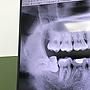

[問卦] 智齒躺這樣是怎樣?

[ Gossiping ]133 留言, 推噓總分: +69

作者: ciiiwa - 發表於 2023/05/09 18:23(2年前)

131Ftio2catalyst: 沒倒勾還行了,快點拔一拔不然大臼齒122.118.9.195 05/10 15:17

132Ftio2catalyst: 後方清不到蛀進去包你痛到升天122.118.9.195 05/10 15:17